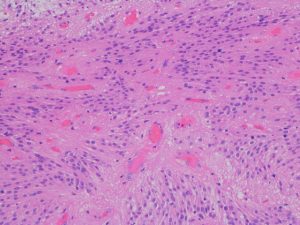

病理と予後

- 病理像では,好酸性の胞体 glassy eosinophilic cytoplasm を有する不整形の巨細胞の存在が特徴です

- 核は,多型で複数核 pleomorohic binucleate to multinucleate,クロマチンは粗,核小体が明瞭で神経節細胞様の大型のものもみられます

- 腫瘍細胞にはGFAP, vimentine, S-100が陽性で,巨細胞はNF, NSEなどが陽性となることがあります

- 血管増殖像はなく,核分裂もなく,組織の異型性に反して臨床的には良性腫瘍の性格を呈します

SEGAの病理像

基本的には,大きくて太った細胞 large plump cells で構成されます。gemistocytic astrocytesにています。

polygonal cells, ganglionic-like cells with a clear nucleoli, and plump large tumor cells resembling gemistocytic astrocytes

multinucleated giant cells

perivascular pseudorosettes, sweeping fascicles